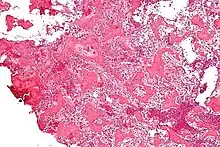

Micrograph of an osteoid osteoma showing the characteristic anastomosing bony trabeculae and osteoblastic rimming. H&E stain.

On histological examination, osteoid osteoma consists of a small (< 1.5–2 cm), yellowish-to-red nidus of osteoid and woven bone with interconnected trabeculae, and a background and rim of highly vascularized, fibrous connective tissue. Varying degrees of sclerotic bone reaction may surround the lesion. Benign osteoblastoma is virtually indistinguishable from osteoid osteoma. The usual appearance included a fibrovascular stroma with numerous osteoblasts, osteoid tissue, well-formed woven bone, and giant cells. The osteoblasts were generally small and regular in shape.[7]